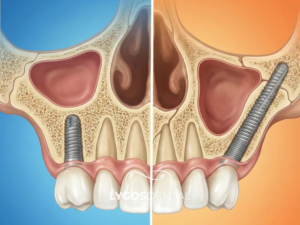

Zigoma implant standart implantlardan çok daha uzun yapıya sahip özel titanyum vidalardır. Bu vidalar üst çenede kemik erimesi olan hastalarda elmacık kemiğine sabitlenir. Elmacık kemiği tıp dilinde zigomatik kemik olarak adlandırılır ve oldukça serttir. Cerrahi işlem klinik ortamında uzmanlar tarafından lokal anestezi veya sedasyon altında yapılır. Açılı bir şekilde yerleştirilen vidalar üst çenedeki protezleri taşımak için güçlü bir temel oluşturur. Çene kemiğinin yetersiz olduğu bölgeler atlanarak doğrudan sağlam anatomik noktalara ulaşılır. İşlem sonrasında genellikle aynı gün içinde sabit geçici protezler vidaların üzerine yerleştirilir. Hastalar aylarca dişsiz kalmadan günlük sosyal yaşantılarına oldukça konforlu bir şekilde dönebilir. Fonksiyonel kayıpların hızlıca giderilmesi psikolojik açıdan hastalara büyük bir moral kaynağı olur.

Standart implantlar genellikle sekiz ile on milimetre uzunluğunda üretilen kısa titanyum vidalardır. Bu kısa vidaların tutunabilmesi için üst çenede yeterli kemik kalınlığı bulunması şarttır. Zigoma implantlar ise otuz ile elli milimetre arasında değişen özel uzunluklara sahiptir. Geleneksel yöntemlerde kemik yetersizse aylar süren sinüs kaldırma ve greft işlemleri planlanır. Elmacık kemiği destekli sistemlerde ise bu uzun ve yorucu cerrahi aşamalar çoğunlukla atlanır. Özel vidalar sinüs boşluğunun yanından veya içinden geçerek doğrudan elmacık kemiğine sabitlenir. Bu sayede tedavi süresi büyük oranda kısalır ve hastanın klinik konforu artar. Standart yöntemlerde dişsiz bekleme süresi uzunken bu sistemde aynı gün protez takılabilir. Maliyet açısından değerlendirildiğinde ek cerrahi işlemleri azalttığı için hastalara avantaj sağlar.

Zigoma implant alt çeneye yapılmaz çünkü elmacık kemiğine sabitlenmek üzere tasarlanmıştır. Bu implant türü üst çenede ciddi kemik kaybı olan hastalarda uygulanır. Zigoma implant, adını zigomatik kemikten alır. Elmacık kemiği yoğun ve güçlü bir yapıya sahiptir. Alt çenede bu anatomik yapı bulunmaz. Alt çene için klasik implant veya farklı ileri cerrahi teknikler tercih edilir. Kemik yetersizliğinde kemik grefti uygulanabilir. Tedavi planı hastanın kemik yapısına göre belirlenir.